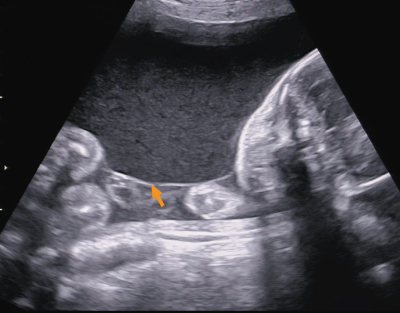

28歳の初妊婦。妊娠 24 週に急激な腹囲の増大と体重増加とを主訴に来院した。妊娠初期の超音波検査で1絨毛膜2羊膜性双胎と診断されている。来院時、子宮頸管長は 40 mm であった。超音波検査で両児間の推定体重に差を認めない。第1児の最大羊水深度を計測した超音波像と両児間の隔壁を示す超音波像とを別に示す。